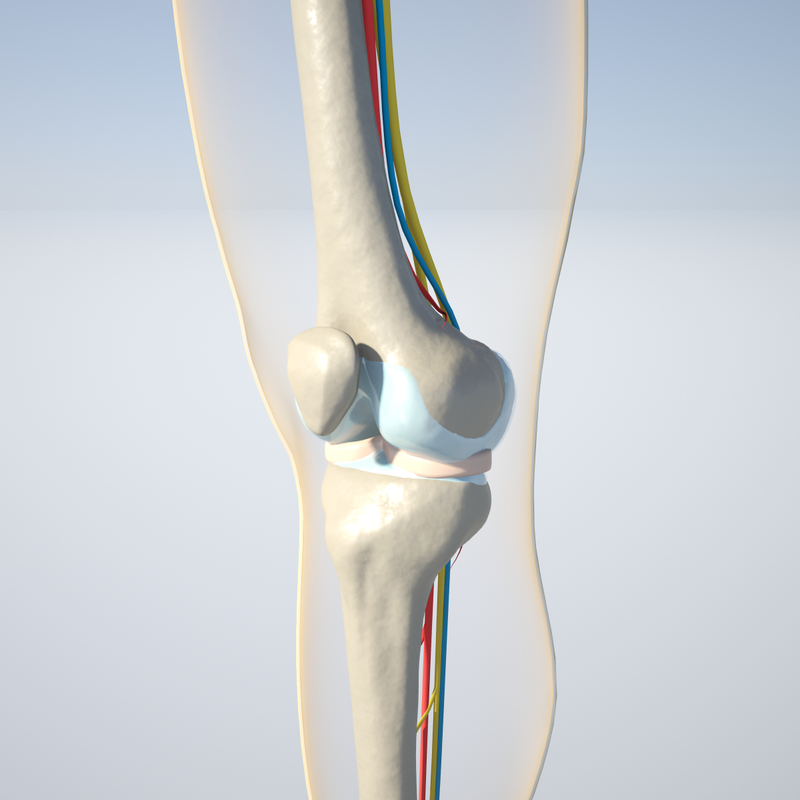

www.turbosquid.comknee turbosquid

www.turbosquid.comknee turbosquid

膝盖3D模型 - TurboSquid 607910

www.turbosquid.comYes, You May Use These For Reference. Edit: 2014-05-05. The Anatomy Is

www.turbosquid.comYes, You May Use These For Reference. Edit: 2014-05-05. The Anatomy Is

![Simplified model of knees - 3D model by threeding.com [e55d9f2] - Sketchfab](https://media.sketchfab.com/models/e55d9f2e211b40dfaa9dd63ff5bde04a/thumbnails/824b404ee4f54f2293e02685ef3d62c0/1024x576.jpeg) sketchfab.comKnee Tendon Diagram - Knee Anatomy - What Are Common Knee Tendons

sketchfab.comKnee Tendon Diagram - Knee Anatomy - What Are Common Knee Tendons

Dynamic Knee Model - Modeling Anatomical Accuracy

dynamicdiscdesigns.comFlüssigkeit Im Knie – Heilpraxis

dynamicdiscdesigns.comFlüssigkeit Im Knie – Heilpraxis

www.nhs.ukThe Knee Joint Anatomy

www.nhs.ukThe Knee Joint Anatomy